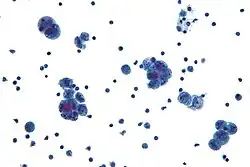

The primary treatment is surgical. FIGO-cancer staging is done at the time of surgery which consists of peritoneal cytology, total hysterectomy, bilateral salpingo-oophorectomy, pelvic/para-aortic lymphadenectomy, and omentectomy. The tumor is aggressive and spreads quickly into the myometrium and the lymphatic system. Thus even in presumed early stages, lymphadenectomy and omentectomy should be included in the surgical approach. If the tumor has spread surgery is cytoreductive followed by radiation therapy and/or chemotherapy.[4]